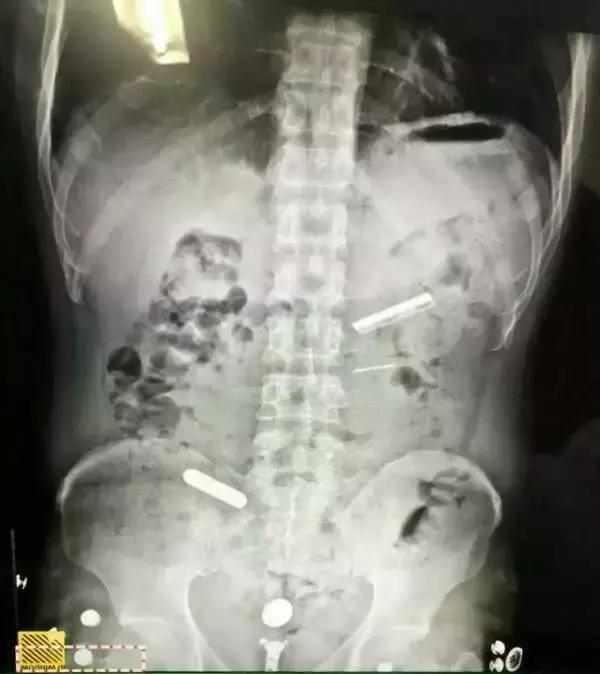

阮某自然也遵循着这个*规则潜**,在前后4次被建设派出所抓获的经历中,每次他的肚子里总是有异物,办案民警每次抓获后只能无奈将其取保候审。“第一次吞是在2008年吧,跟着别人学的,拿胶带纸在刀片外面裹几层,以防割破身体内脏。”被刑事拘留后的阮某说,“因为这些物品会在一段时间内自然排出体外,但也有钢针类金属因挂在肠壁上长时间难以排出。”在不确定异物是否被排出体外的情况下,他每隔几天就要吞入一枚刀片或者钢针,以逃避法律制裁。

3月15日,建设派出所民警在阮某的住所将其抓获,并马上将他带到第二医院检查,在X光的照射下,藏于阮某体内胃部和肠道内的2枚单面刀片和1枚钢针非常醒目。通过胃镜手术,一枚刀片被取出,后又通过服用粗纤维蔬菜及石蜡油润肠,另外两样异物也终于从阮某体内被排了出来。3枚异物的长度都大约在4厘米。3月21日,阮某被成功送押到嘉兴市看守所,经审讯,他交代了为满足毒资实施扒窃的犯罪事实。